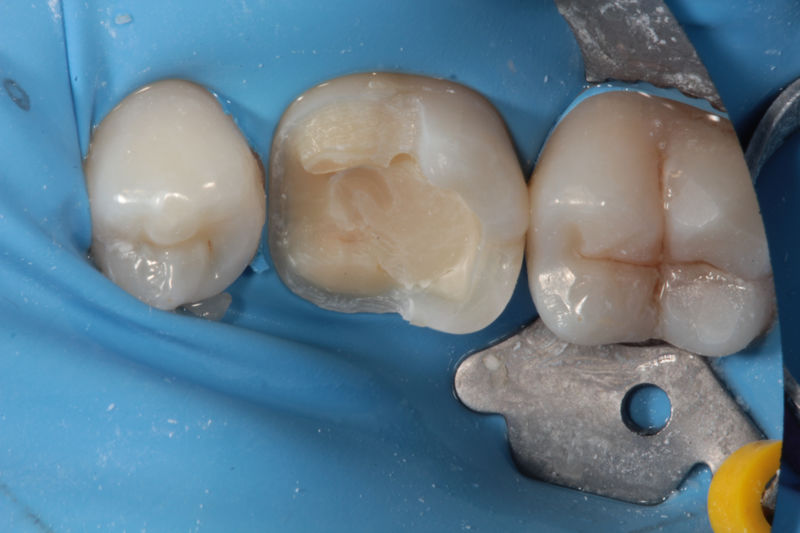

Disciplina fundamental de la Odontología enfocada en el diagnóstico, prevención y tratamiento restaurador de las piezas dentales que han sufrido daños. Su objetivo principal es devolver al diente su equilibrio biológico, funcional y estético cuando su integridad ha sido alterada. Resinas directas, incrustaciones, coronas.

Restauraciones fabricadas en el laboratorio con materiales estéticos, los cuales cubren de manera parcial dientes posteriores. Se utilizan primariamente para restaurar dientes con caries, fracturas y/o defectos amplios. Para poder enviar el caso al laboratorio se toman impresiones utilizando materiales de impresión o técnicas modernas digitales.

La restauración de un diente tras una endodoncia, es crucial para su supervivencia a largo plazo, ya que el procedimiento puede debilitar la estructura dental. El tipo de restauración elegido depende principalmente de la cantidad de estructura dental remanente después de la endodoncia. Principalmente se usan incrustaciones, coronas y/o postes.